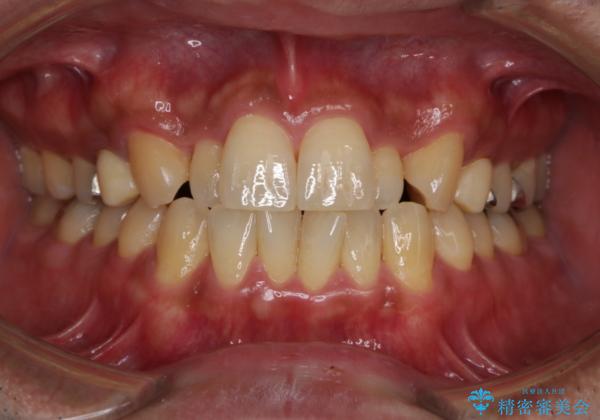

- お口の中にある銀歯を無くしたいとご相談にいらした方です。

適合の良いセラミックにてやり替えを行いました。

矯正治療もご提案しましたが、ご希望されなかったため、今回は被せ物のやり替えのみ行っております。